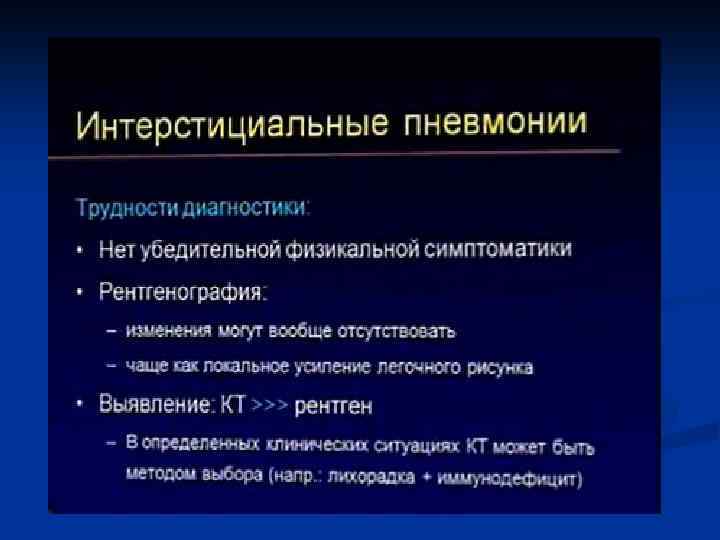

Интерстициальная пневмония

Интерстициальная пневмония n n n n Хуже диагностируются чем паренхиматозные Чаще – постгриппозные Вяло текут ОАК – почти норма Субфебрилитет Жалобы на недомогание, сухой кашель, вялость Это продуктивное воспаление (лечится тяжело)

Интерстициальная пневмония n n Характеризуется воспалительной инфильтрацией интерстиция Вызывающие ее микроорганизмы: вирусы, микоплазма, рикетсии, приводят к отеку и лимфацитарной инфильтрации стенок бронхов, Далее распространяется по междольковым перегородкам. Лимфоцитарная инфильтрация перибронхиальных альвеол, что придает сходство с очаговой ПН

Интерстициальная ПН - ретикулярные = сетчатые изменения легочного рисунка - преимущественно центральным = прикорневым распределением - могут быть очаговые сливающиеся уплотнения легочной ткани

КТ-семиотика интерстициальной пневмонии n n n Понижение прозрачности легочной паренхимы по типу «матового стекла» Утолщение внутридолькового интерстиция Утолщение междолькового интерстиция Утолщение перибронховаскулярного интерстиция Тракционные бронхо- и бронхиолоэктазы Изменения по типу «сотового легкого»